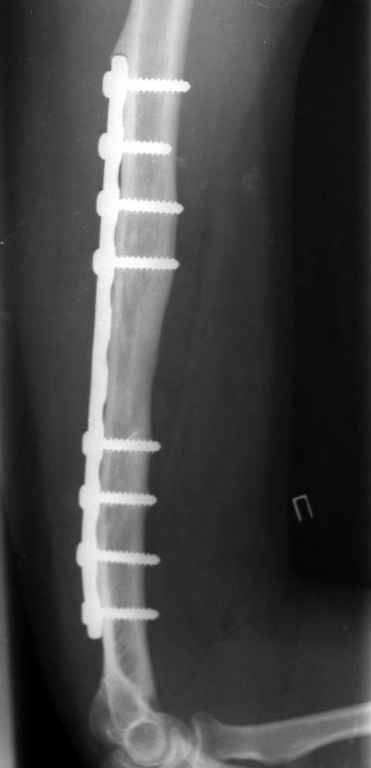

Владимир. Выделяем свои малоберцовую кость практически полность. Выпиливаем замок там и тут. Синтез. Нетипичный случай, но перестраивается хорошо даже диафиз. С уважением Дрягин